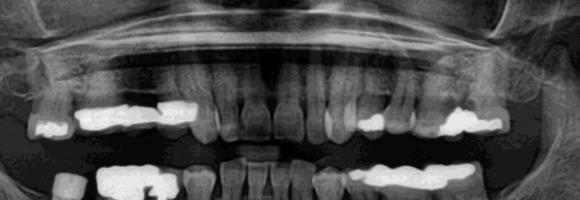

Immediate Implant Placement

A molar either maxillary or mandible always represents a little difficult and tricky scenario for implant placement immediately after extarction. There is always some sacrifice for the location, angle etc. however you save some time and patients go through a procedure once and it is a reliable method of replacing a tooth, when feasible. Dental implant is always a compromised replacement and a tooth restored with immediate placement is not any different.